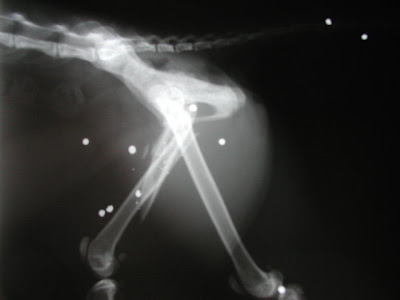

Dr. Clary arrived with his entourage for the surgery just prior to 11am - and Shmi was pretty much sedated the entire time he was there. Finally, with her feeling no pain, he was able to do a thorough exam and his findings were rather grim. He pointed out where it looked like part of her fractured bone was already trying to attach to the wrong place, and was able to show just how much shortened the injured leg was in comparison to her good leg. He explained that the difficulty with this surgery wasn't going to be the break itself, but rather the amount of time since the injury.

For the next THREE and a HALF HOURS, Dr. Clary and his assistant, Margaret, worked tirelessly to piece Shmi's leg back together. Since Shmi is a young cat, in otherwise excellent health, her bones had no problem trying to heal themselves and already started to regenerate new bone. Unfortunately, since the fractured bones weren't anywhere near their proper alignment, the new growth was actually a hindrance and had to be meticulously scraped away. A pin was placed through the length of the bone - but another discovery made the plan a little trickier than expected. Unable to be seen on the x-ray, a segment of Shmi's femur had become completely broken off from

either end of the bone and was not in a usable form. Dr. Clary decided that a plate would be needed and this would be her best chance for a smooth recovery. He inserted a plate along side the re-aligned portions of the femur and screwed in 11 screws. One was not able to be inserted due to the missing bone fragment. Shmi's femur will grow back from either end and reattach over time. The plate, unless any unforeseen complications should arise, will stay in her leg for the rest of her life. She will not be able to go through any metal detectors ;-)